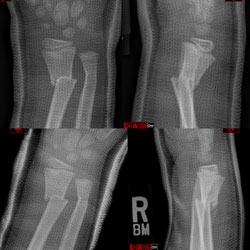

A Quality Improvement Initiative to Reduce Radiation Dose During Cast Treatment for Infantile Scoliosis

Joseph Khoury, Cheryl Lawing, Maureen Maciel, Kyle Achors, Fontenot Philip